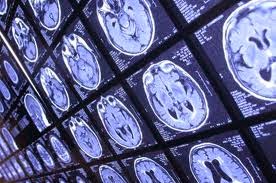

A Crash Course in Medical Imaging

Oddly enough, there’s been a surprising lack of content about medical imaging on a blog with medical imaging in its title. So in order to fill that void, I’ll be providing a brief history on the development of the clinical technique used to visualize the human body.

- Ultrasound – Uses sound waves that are able to penetrate cellular tissue. Once they reflect off the body’s internal organs, the vibrations generate an electrical pulse which can then be reconstructed into an image.

- PET-CT Scan – Positron emission tomography (PET) uses compounds that emit positrons when they decay rather than gamma rays. It is now combined with a computed tomography (CT) device to generate a high-resolution image displaying sectioned layers of the scanned area.

- MRI – A Magnetic Resonance Imaging scanner runs a strong magnetic field through the body, aligning hydrogen protons. As the protons return to their original position in the atom, they generate radio waves, which are then picked up by the scanner and used to create an image based on signal strength.

Fast-forward to present day and over 70 million CT scans, 30 million MRI scans and 2 billion X-rays have been performed worldwide! The field of medical imaging is still growing by the day, with ongoing research leading to new developments.